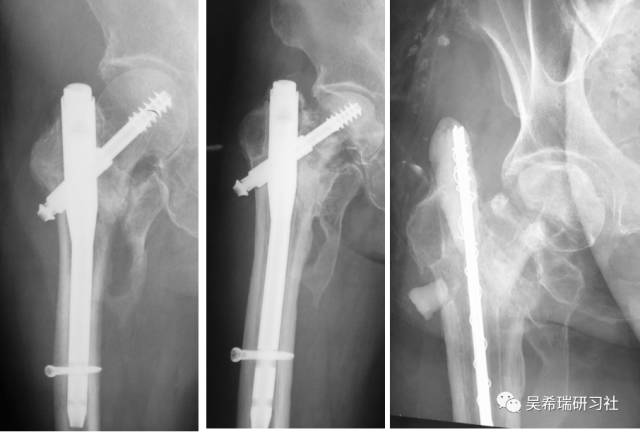

髓内钉固定后1.5年迟发性低度感染取出髓内钉清理髓腔自制骨水泥髓内钉占位器15天愈合

TIPS:清理髓腔是关键全髓腔感染可以用扩髓器占位器15天左右取出,时间久成为异物全身应用敏感抗生素